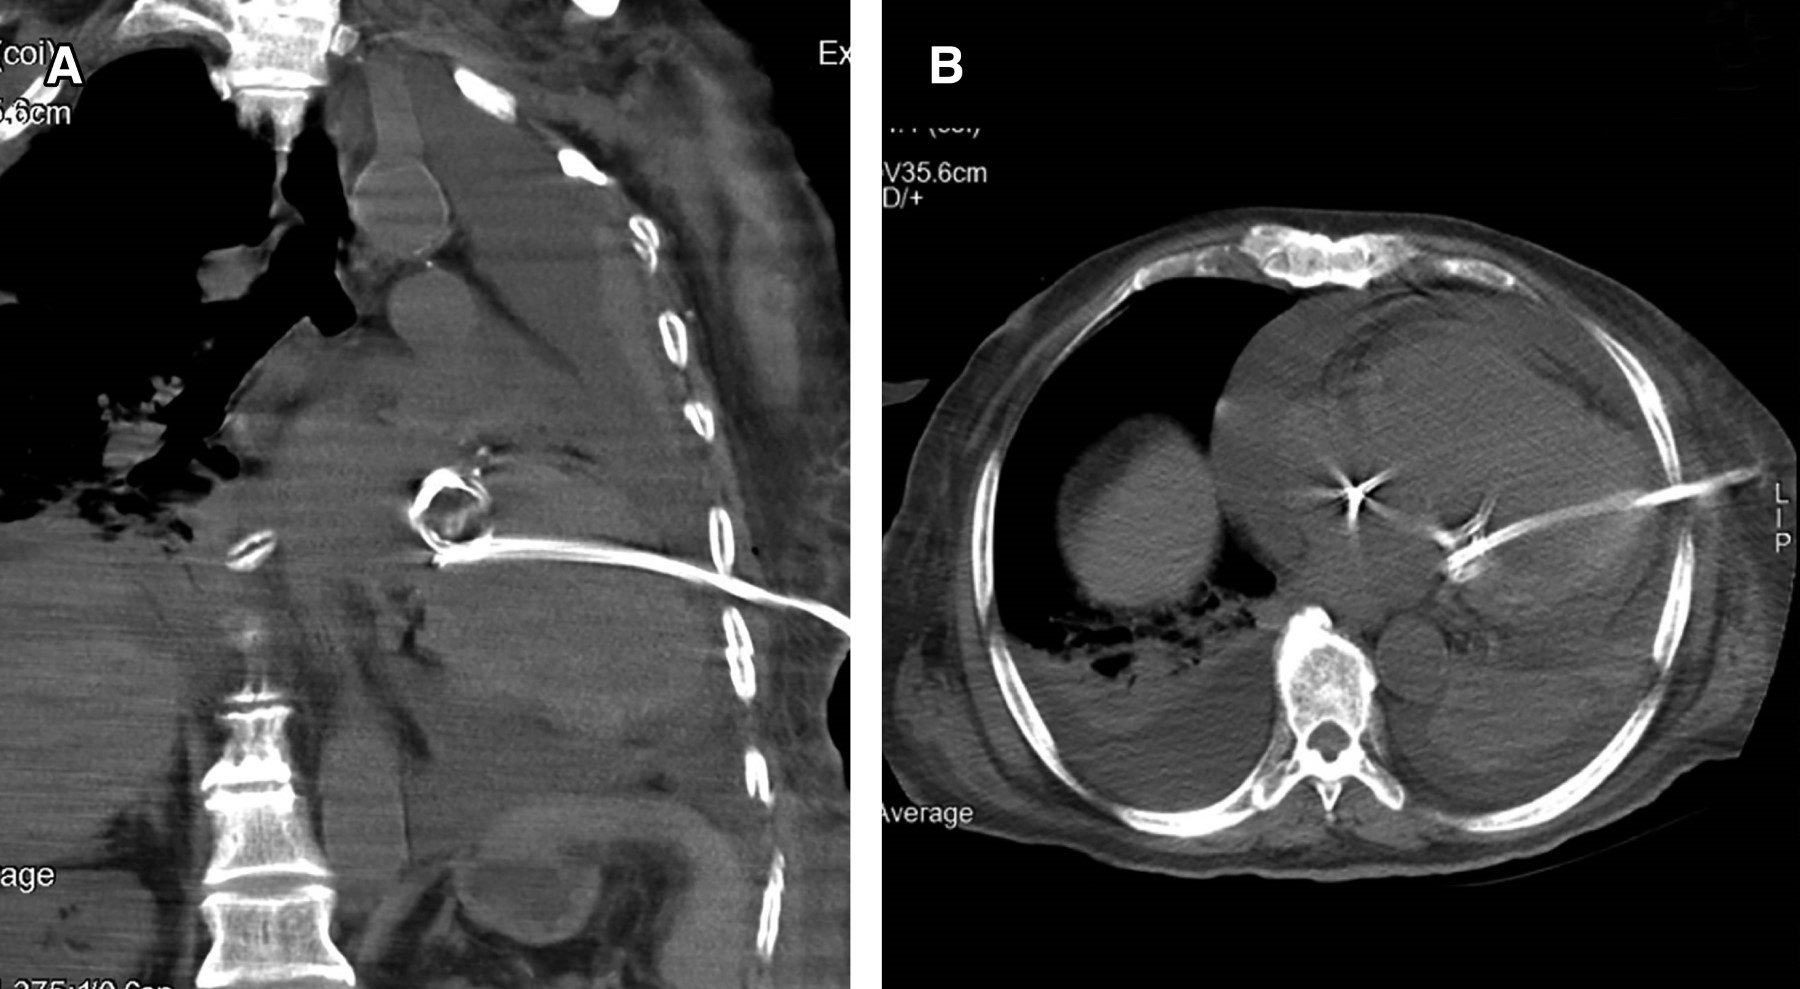

Presentamos el caso de un paciente masculino quien fue tratado en el departamento de urgencias por derrame pleural izquierdo mediante un drenaje torácico. Posterior a la colocación se obtuvo gasto hemático inmediato. Se realizó tomografía de tórax, así como ecocardiograma que evidenció posición de tubo de drenaje en ventrículo izquierdo. Se realizó intervención quirúrgica para el retiro de catéter mediante toracotomía anterior izquierda con extracción exitosa.

Figura 2

Figura 3